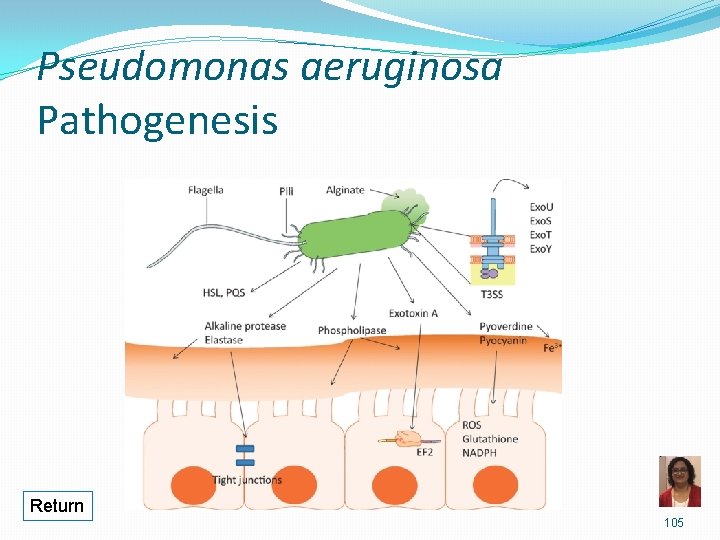

Pseudomonas aeruginosa • Attachment to epithelial cells via pili &/or adhesins Avoiding host defense Alginate (polysaccharide) capsule/slime layer formation of microcolonies protection from immune response Biofilm formation Inflammation Endotoxin/LPS • Tissue damage via extracellular enzymes and toxins Exotoxin A ADP-ribosylation of EF-2 stops protein synthesis cell death • Break down of host cells, tissues, proteins, lipids Elastase, alkaline phosphatase, phospholipase C, Exoenzyme S

Pseudomonas aeruginosa Pathogenesis Return 105